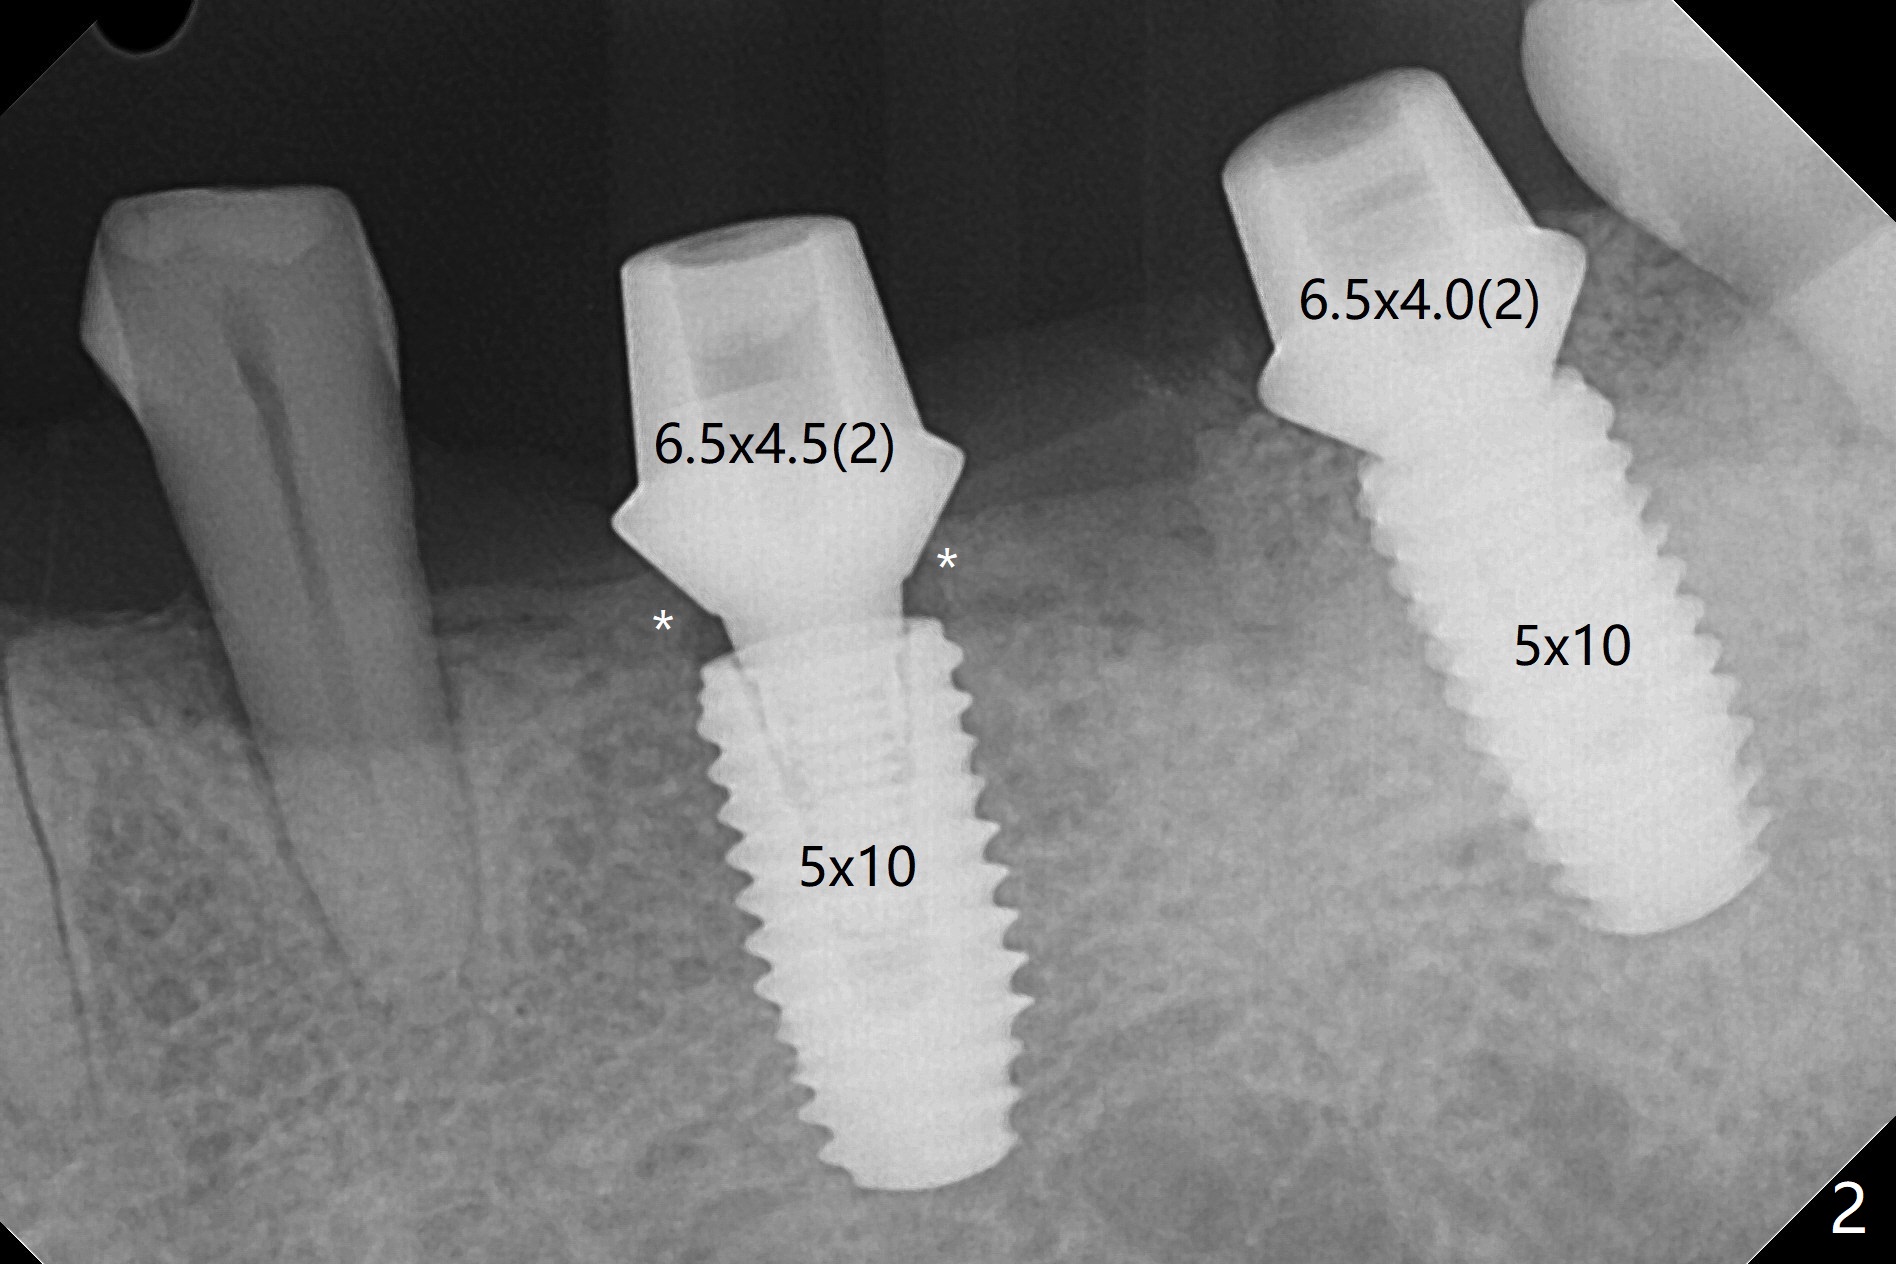

Re-analysis of preop CT reveals extensive bone loss around #18 (Fig.1 (lingual view)). Blood is withdrawn for sticky bone. After implant placement (Fig.2), sticky bone is placed at #18 (Fig.3 red dashed line (yellow: superior border of the Inferior Alveolar Canal)). PRF membrane and an immediate provisional FPD (#18-20) further keep the bone graft in place for healing. Four months postop, the patient reports difficulty in mastication on the left and requests extraction of the tooth #20 for implant (Fig.4). The implant will be placed lingually, while socket shield will be performed buccally (Fig.5 S) to keep bone graft in place. The implant at #19 is equicrestal (Fig.6); the one at #18 is apparently supracrestal buccally (Fig.7). Since there is a lot of scattering from nearby crowns, the implant at #20 will be placed free hand. To overcome the thick dense lingual plate (Fig.8 L), osteotomy is initiated (Fig.9 red line) in the middle of the lingual wall of the extraction socket (black area) on the top of the socket shield (S). After the last drill (3.5x11.5 mm, Fig.10 pink) and before 4x11.5 mm implant, use Lindamann bur to remove the coronal portion of the lingual plate (Fig.11 red line) to prevent implant buccal deviation.